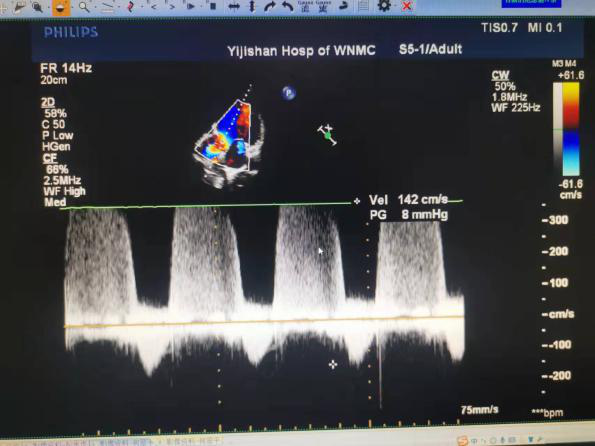

近日,皖南医学院弋矶山医院心脏大血管外科张大发教授团队,运用VitaFlow Liberty™经导管主动脉瓣膜系统成功为一例主动脉瓣重度反流、二尖瓣、三尖瓣中度反流,左心显著增大,瓣环、流出道极限值且极低EF的患者成功实施了TAVR手术。

半年来偶感胸闷,心慌,近一个月来因肺部感染导致胸闷心慌加重,就诊于当地医院;超声心动图示:升主动脉硬化并扩张,重度主动脉反流,左心明显增大,中度二尖瓣反流,中度肺动脉高压伴中度三尖瓣反流,左室收缩功能减退,EF值30%。当地医院建议转院进一步诊治,遂至皖南医学院弋矶山医院就诊,诊断为主动脉瓣重度关闭不全,二尖瓣中度关闭不全,心功能IV级。